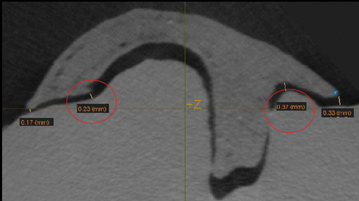

Fig 3. A 3D printed scaffold was designed using CAD software to fit a peri-osseous defect in a human patient. The scaffold consisted of a region with channels designed to support oriented PDL tissue formation and a region for the regeneration of osseous tissue. Fig 3: baseline;

Fig 4: defect model; Fig 5 through Fig 7: internal, tilted, and side views of scaffold, respectively; Fig 8 through Fig 10: coronal, middle, and apical

angles, respectively; Fig 11: cross-section diagram; Fig 12: labial scan image. (Images reprinted with permission from Rasperini G, Pilipchuk SP, Flanagan CL, et al. J Dent Res. 2015;94[9 suppl]:153S-157S.)

Figure 3

Fig 4. A 3D printed scaffold was designed using CAD software to fit a peri-osseous defect in a human patient. The scaffold consisted of a region with channels designed to support oriented PDL tissue formation and a region for the regeneration of osseous tissue. Fig 3: baseline;